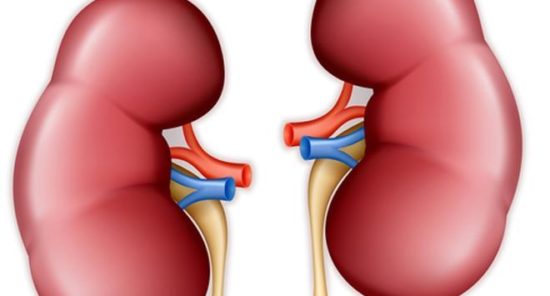

Строение почек человека: Фото и описание